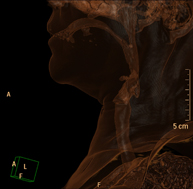

Prueba radiológica que consiste en obtener imágenes del cuello de alta definición anatómica mediante el empleo de un equipo de TC (Tomografía Computarizada). Indicaciones: estudio de tiroides, control de tumores tratados, estudio de ganglios, infecciones y abscesos. - TC Laringe

Prueba radiológica que consiste en obtener imágenes de la laringe de alta definición anatómica mediante el empleo de un equipo de TC (Tomografía Computarizada). Indicaciones: afonía súbita o crónica, dificultad respiratoria. - TC Órbitas

Prueba radiológica que consiste en obtener imágenes de las arterias carótidas del cuello de alta definición anatómica mediante el empleo de un equipo de TC (Tomografía Computarizada) y la inyección de contraste intravenoso. Posteriormente, las imágenes son reconstruidas en tres dimensiones (3D). Indicaciones: accidente vascular cerebral agudo, accidente vascular transitorio, soplo carotídeo. - TC Columna cervical